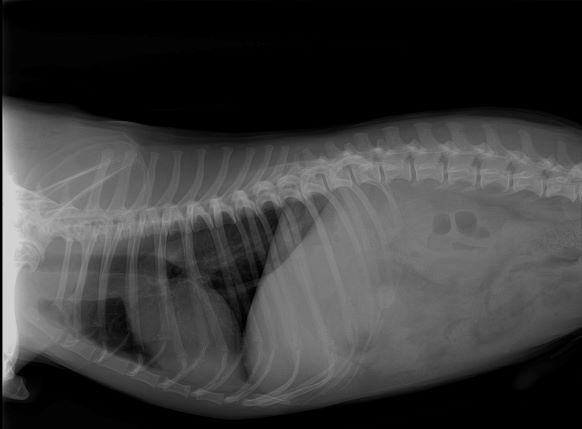

We are capable of interpreting:

Bone/Soft Tissue Injuries

OFA evaluations (hips and elbows)

Pregnancy Counts for Puppies/Kittens